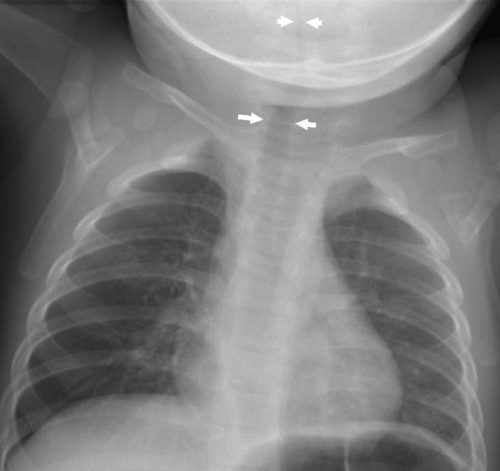

新生児・乳幼児によくみとめられるサイン。いずれも前縦隔にある胸腺を示している。胸腺は免疫器官として重要で、生後活発に活動しているため、この年齢では大きく、他の縦隔腫瘍と鑑別するのに役立つ。肋骨に圧迫されて波打つような形状がtjymic wave sign 、帆のように三角に突出してみえるのが sail sign 。

[参考例] ①透過性不良の間質性肺炎を示唆する写真だが、sail signをみとめる。同時に気管が右へ弯曲している。正面像で撮影できていないが、実際の臨床の場ではこのようなレントゲン像が少なくなく、読影に影響されてはいけない。 [参考例] ②右肺への張り出した陰影に肋骨部の凹みがあり胸腺と判断できる。 [参考例] ③縦隔の拡大があり右辺縁はwaveしていて胸腺と理解できる。(左肺野に浸潤影をみとめシルエットサイン陽性) [参考例] ④胸腺の典型例 epicardial fat(心臓横隔膜の脂肪組織) 心臓には脂肪組織が沈着していてレントゲン像として左右の心臓下部に均等な陰影として出現。右側には下大静脈の陰影もみとめるので銘記しておくとよい。 beginner’s triangle(正常でも異常に見えやすい右下肺内側のこと)(medicina Vol. 50 No.12 2013-11 一色論文 )。